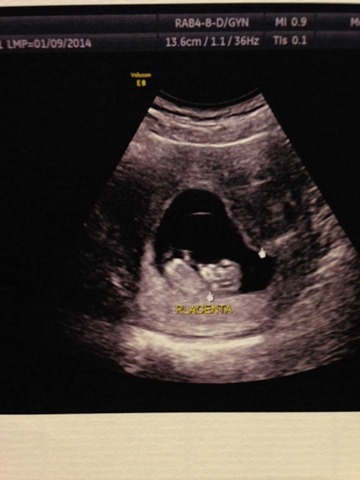

沒錯~妳們沒有看錯,Jan懷孕嚕(ಠ .̫.̫ ಠ)))

(yoyoyo看到手手與腳腳了呢,我會是天秤座寶寶呢~)

連寶寶都舉起手來歡呼喔!哈